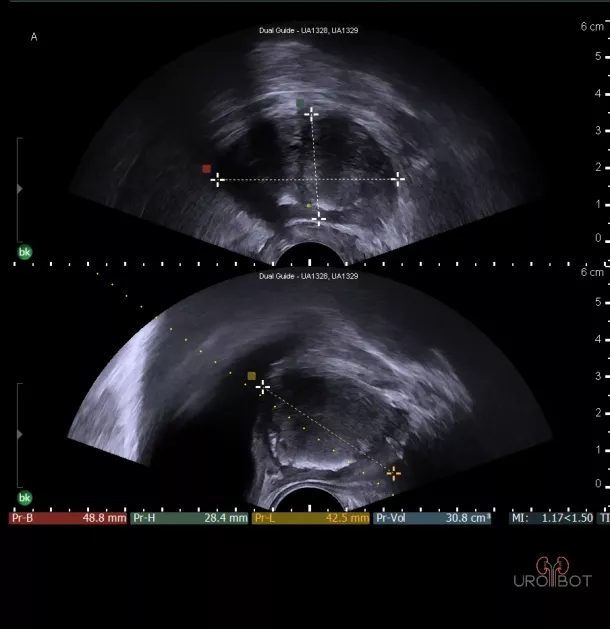

Prostata: Normalbefund

Auf diesem Bild erkennt man die Prostata in zwei Ebenen mit Hilfe einer in den Enddarm eingeführten Ultraschallsonde.

Prostata: Normalbefund

Auf diesem Bild erkennt man die Prostata in zwei Ebenen mit Hilfe einer in den Enddarm eingeführten Ultraschallsonde.